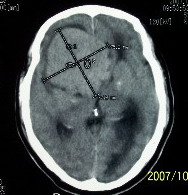

f    29岁   头闷  头晕1月余

脑膜瘤可能性大

考虑室管膜瘤可能性大,建议增强或mri

鞍上脑膜瘤

肿瘤累及颅底前颅窝,部分层面见散在钙化,中心坏死。支持:脑膜瘤!

这么大,鞍上压迫那么厉害,梗阻也比较重没有视力及其他症状吗?从肿瘤本身表现看,支持考虑颅底脑膜瘤

肿瘤长入侧脑室,侧脑室明显扩大, 病灶边界清楚,其内可见低密度坏死区,中枢神经细胞瘤?室管膜瘤?

镰旁高密度灶,中间低密度坏死区,周围水肿较轻,支持脑膜瘤诊断,建议结合增强扫描。

右额叶底部巨大等低混杂密度肿块,边界清楚,周围水肿轻度,明显占位效应。蝶鞍扩大,部分骨质破坏。

考虑脑膜瘤,建议增强扫描进一步检查。

蝶鞍受压吸收,可以排除室管膜瘤。肿瘤最大层面不在蝶鞍可以排除垂体瘤。支持脑膜瘤